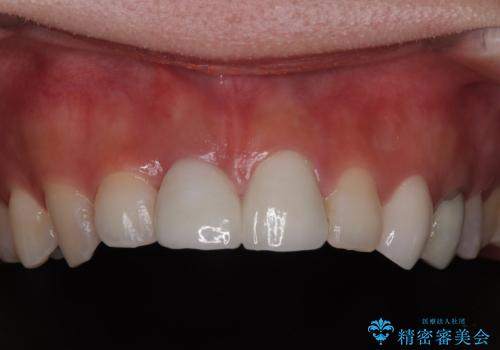

抜歯を避けられない場合でも、「即日でインプラント治療+仮歯装着」により見た目を損なわないで治療を終えることができました。

抜歯をしてインプラントを埋入してから、4か月で最終補綴物(オールセラミッククラウン)の装着まで終えることができ非常に満足いただきました。